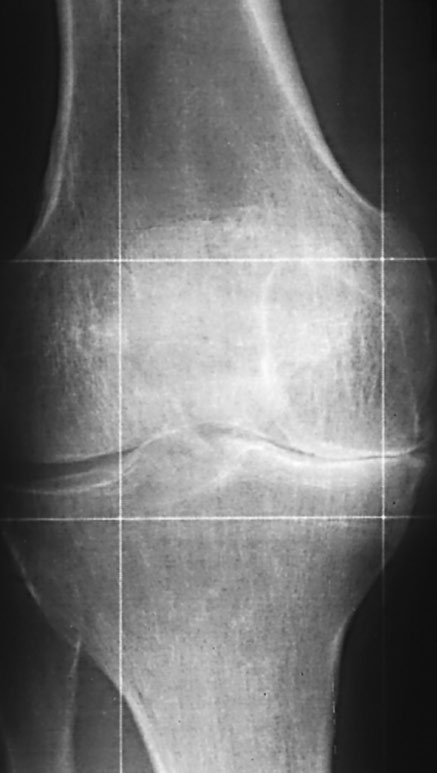

Eine Arthrose liegt vor, wenn via Radiologie die Degeneration und Destruktion des hyalinen Gelenkknorpels festgestellt wird (▶ Abb. 1 und Abb. 2). Die Pathologie imponiert im Röntgenbild mit typischen Zeichen:

- Verschmälerung des Gelenkspalts (Knorpelverschmälerung)

- subchondrale Sklerosierungen

- Zysten- und Osteophyten-Bildung

Gonarthrose. Neben der Verschmälerung des Gelenk-

spaltes imponieren v. a. Veränderungen im subchondralen

Knochen (Aufhellungen). Quelle: Ronny Petzold.